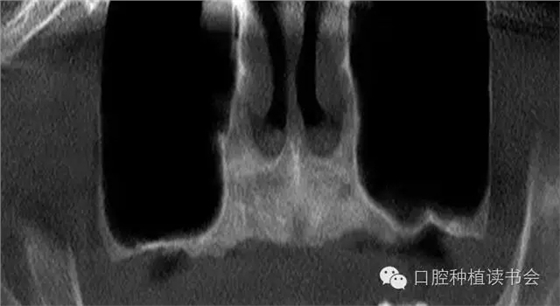

上頜竇氣化的現(xiàn)象主要來(lái)自先天因素和生理病理性因素,有的病人雖然年輕,但上頜竇腔較大,后牙牙根幾乎伸進(jìn)上頜竇。隨著年齡增大、磨牙缺失,由于上頜竇處于負(fù)壓狀態(tài),尤其是缺牙后缺少來(lái)自牙槽脊的功能刺激,氣化現(xiàn)象會(huì)更嚴(yán)重,加之原有竇腔較大,就表現(xiàn)為巨大的上頜竇腔,甚至竇底與鼻底在同一水平(圖2)。有研究表明,上頜竇容積在青少年階段隨年齡而變化,中老年階段達(dá)到穩(wěn)定狀態(tài),氣化系數(shù)無(wú)增齡性改變。上頜竇竇腔平均最大容積為:38*33*38mm(Chih-Long,2014)。上頜竇容積和牙槽骨骨量呈負(fù)相關(guān),上頜牙全部脫落促進(jìn)上頜竇變形,上頜竇容積有減小趨勢(shì)。上頜骨的老化特點(diǎn)是一個(gè)漸變的過(guò)程,步入中年期開(kāi)始進(jìn)行重塑,而老年期上頜骨形態(tài)變化較小。

總結(jié)上頜竇腔的骨性結(jié)構(gòu)特點(diǎn),人們發(fā)現(xiàn)上頜竇底并一定是平坦的,有些竇底會(huì)有斜坡?tīng)畹那闆r(圖3)。而上頜竇的分隔情況發(fā)生率可達(dá)上頜竇數(shù)量的27.7%,病人數(shù)量的37%。分隔在上頜竇前部占22.5%,中部占45.9%,后部占31.5%(Park,2011)(圖4)。所以SFE的障礙之一就是骨性結(jié)構(gòu)的變異,給提升技術(shù)和工具帶來(lái)挑戰(zhàn)。